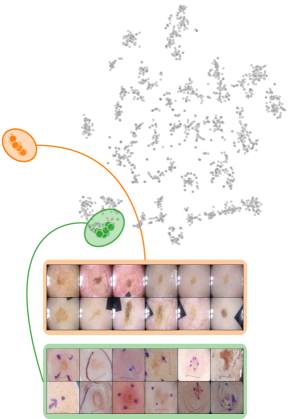

Both input and latent relevance clustering require subsequent human supervision to determine whether outlier clusters represent valid or spurious behavior. To semi-automate this process, Anders et al. [3] propose using Fisher Discriminant Analysis [37] to rank class-wise clusterings by linear separability, while Dreyer et al. [27] computes similarities between prototypes. The results of clustering approaches can serve as an initial set for bias modeling methods outlined in Sec. 3.2, which can be refined iteratively. An example outlier cluster of latent relevances is shown in Fig. 4 (top), with all samples containing the spurious band-aid concept.

where reduces the dimension to , and the pairwise distance function is applied along all channel dimensions in the latent representation , either given by activations or relevance scores for layer . Note that this approach assumes over-parameterization resulting in redundant neurons, allowing to distinguish between similar and dissimilar concept representations. An example is shown in Fig. 4 (bottom), where latent relevance scores from a ResNet50 model trained for melanoma detection are used to identify outlier concepts, specifically a cluster focusing on band-aids rather than clinically relevant features. Notably, Eq. 3 can easily be extended to find outlier directions instead of neurons. Specifically, this involves a linear transformation of latent representations using the directions of interest, e.g., obtained in unsupervised manner as described in Sec. 3.1.

Given the fitted models, we apply bias identification methods introduced in Sec. 4 to detect the expected spurious model behavior. Throughout this section, we focus on the ResNet50 model trained on ISIC2019 with various confounders. We further limit our analyses to samples from the melanoma class to prevent that clustering model behavior results in clusters representing different classes, and instead allowing us to identify spurious sub-strategies for predicting the considered class.

Data Perspective

We first apply SpRAy in input and latent space, computing input feature importance scores using LRP summed over color channels. To obtain latent relevances, we use intermediate relevance scores in the LRP computation process after the (out of four) residual block, max-pooling over spatial dimensions to yield relevance scores for layer with channels. The clustering of pairwise cosine distances between heatmaps is shown in Fig. 6 (top left). Detected outlier clusters contain samples with spatially coherent biases, e.g., the black circle around the lesions originating from microscopes (). In contrast, clustering latent relevance scores reveals more complex, less spatially dependent clusters, as shown in Fig. 6 (top right), including the ruler artifact () and the microscope (). Compared to those in input space, the cluster for the microscope in latent space represents a more diverse high-level concept. In the input space visualization, we further highlight samples from the ruler cluster detected in latent space. Instead of forming a cluster, they spread across the entire embedding space, indicating that the bias is too complex to be detected in input space.